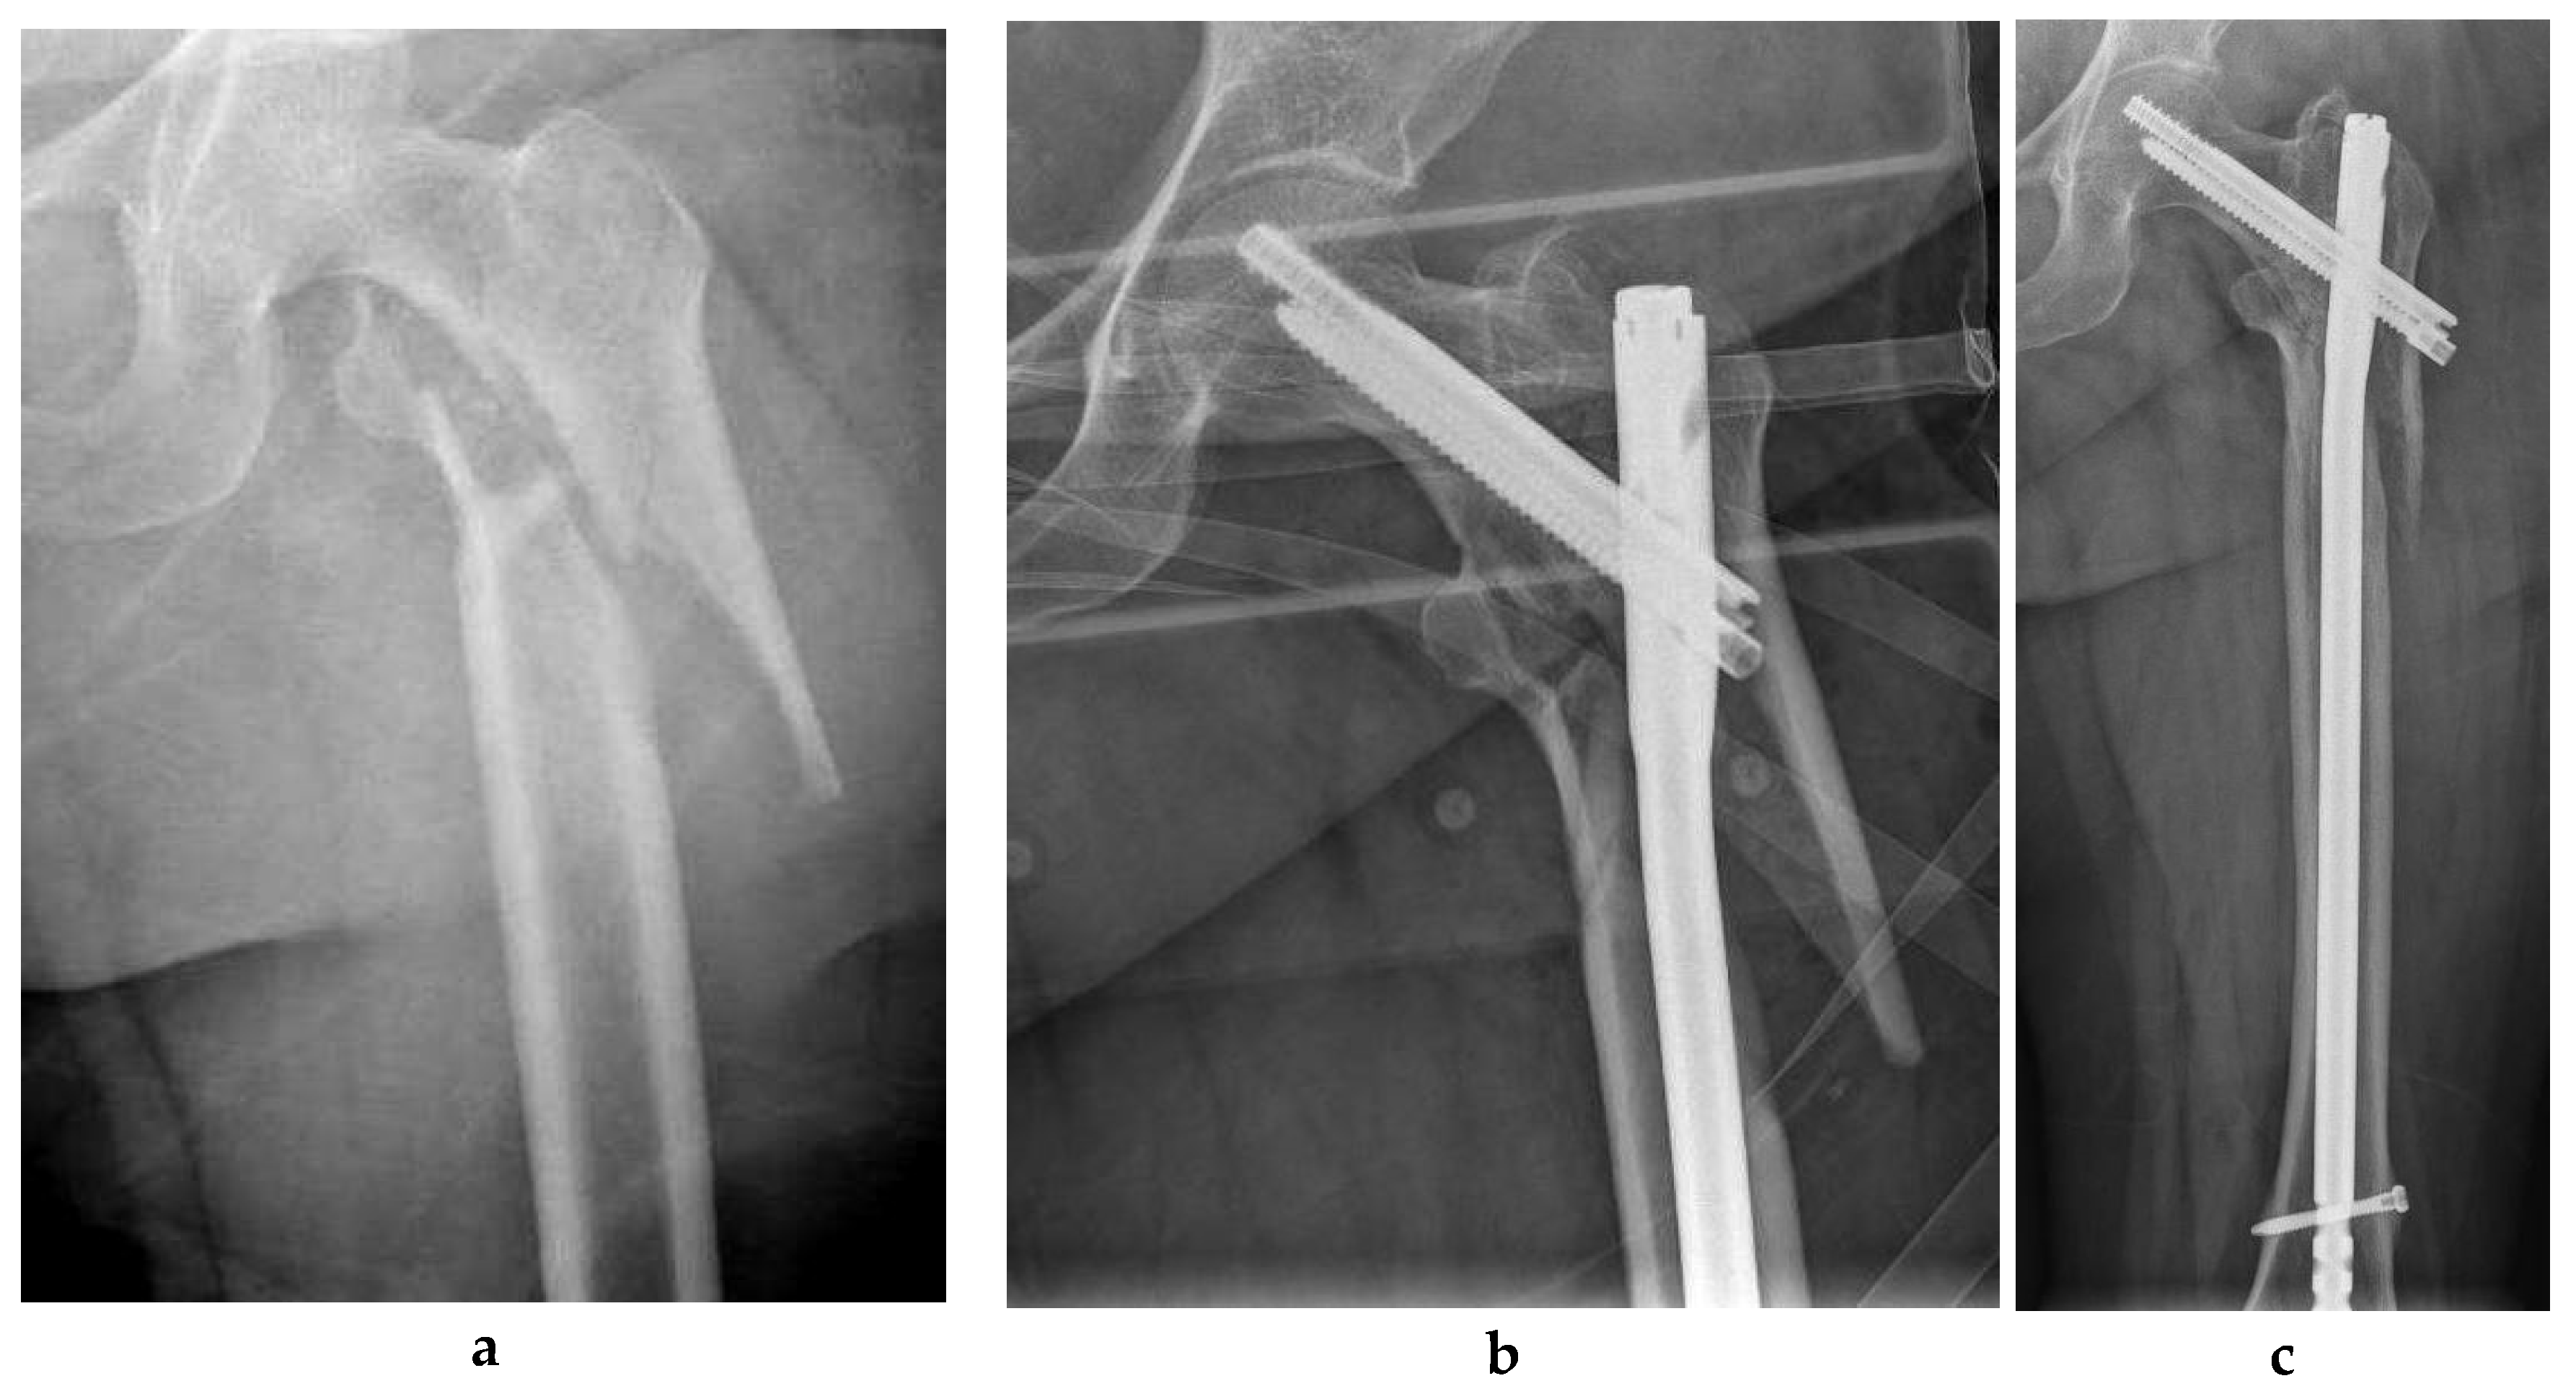

Goodnough et al. compared the revision risk between the TFNA and its prior-generation forebear, the Trochanteric Fixation Nail (TFN) (DePuy Synthes, Synthes, Oberdorf, Switzerland). They found that the TFNA had an overall revision rate that was similar to that of the earlier TFN, with implant breakage being a rare revision reason for both groups. These authors found that the TFNA was associated with a higher risk of revision for non-union (HR, 1.86 [95% CI, 1.11 to 3.12]; p = 0.018). TFNA had an overall revision rate that was similar to that of the earlier TFN, with implant breakage being a rare revision reason for both groups [16]. Finally Swift et al. compared the Synthes TFN and the Zimmer Natural Nail (ZNN). No differences in rates or modes of failure were identified between the TFN and ZNN constructs [17]. Figure 2 shows an ITF fixed with a Trochanteric Fixation Nail (TFN) (DePuy Synthes, Synthes, Oberdorf, Switzerland).

Figure 2. (a-i). Intertrochanteric fracture (ITF) in a 35-year-old man (a); fracture was fixed with a Trochanteric Fixation Nail (TFN) (DePuy Synthes, Synthes, Oberdorf, Switzerland) (b); radiograph 18 months after surgery showed nonunion of the fracture (c) (d); exchange nail and bone grafting was performed (e); 12 months later nonunion was not achieved (f) and (g); new fixation with blade-plate and bone grafting was carried out (h); image taken 24 months later: bone healing was achieved eventually (i).